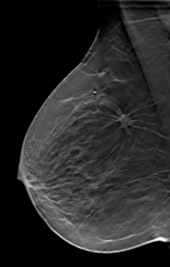

Mammographie-Physik

Seit der Einführung des österreichischen Mammographie-Screenings im Jahr 2009 ist unser Zentrum kontinuierlich an der Entwicklung und Erweiterung von Methoden zur Verbesserung der Qualitätsbeurteilung für Mammographiegeräte beteiligt. Die enge Zusammenarbeit mit dem Referenzzentrum für technische Qualitätskontrolle des Mammographie-Screenings führte zu einer Reihe von interessanten Publikationen und vielversprechenden Projekten. Kürzlich konnten wir im Rahmen eines von der FFG geförderten Projekts einen Prototyp zur Bewertung der Bildqualität für die Tomographie entwickeln. Dieses Phantom wurde bereits von der FDA (U.S. Food and Drug Administration) zugelassen und wird Teil der neuen österreichischen Standards für die Qualitätskontrolle in der Mammographie sein.